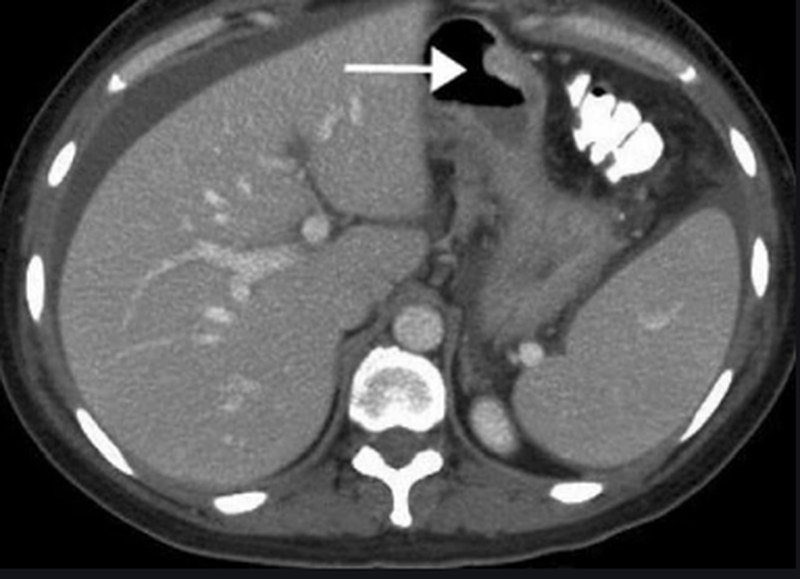

Что покажет МРТ желудка

Органы брюшной полости служат для обеспечения человеческого организма энергией путем переваривания пищи и снабжая организм питательными элементами. На сегодняшний день значительно ухудшилось качество потребляемых продуктов, а также неблагоприятная экологическая обстановка, неправильное питание, многочисленные стрессы, нарушение режима питания - все это подвергает органы брюшной полости серьезной нагрузке, и, как следствие, работа органов брюшной полости дает сбой и приводит к появлению каких-либо заболеваний. Чтобы точно диагностировать патологии желудочно-кишечной тракта, медики и назначают сделать МРТ желудка или КТ органов брюшной полости. Оба этих сканирования хорошо покажут:

• язвенные образования;

• болезнь Крона;

• опухолевые процессы;

• врожденные патологии и деформации;

• признаки тканевых инвазий и некрозов;

• воспалительные процессы в кишках.